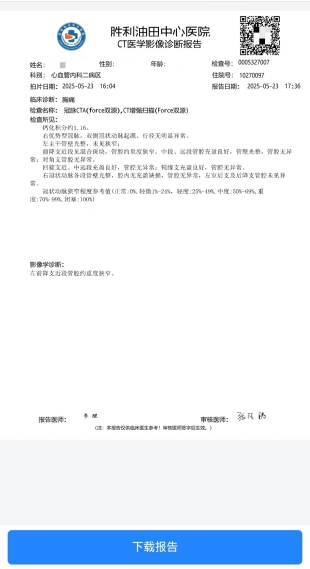

排栓前:左前降支近段管腔约中—重度狭窄 排栓后:到医院检查不符合心脏支架标准